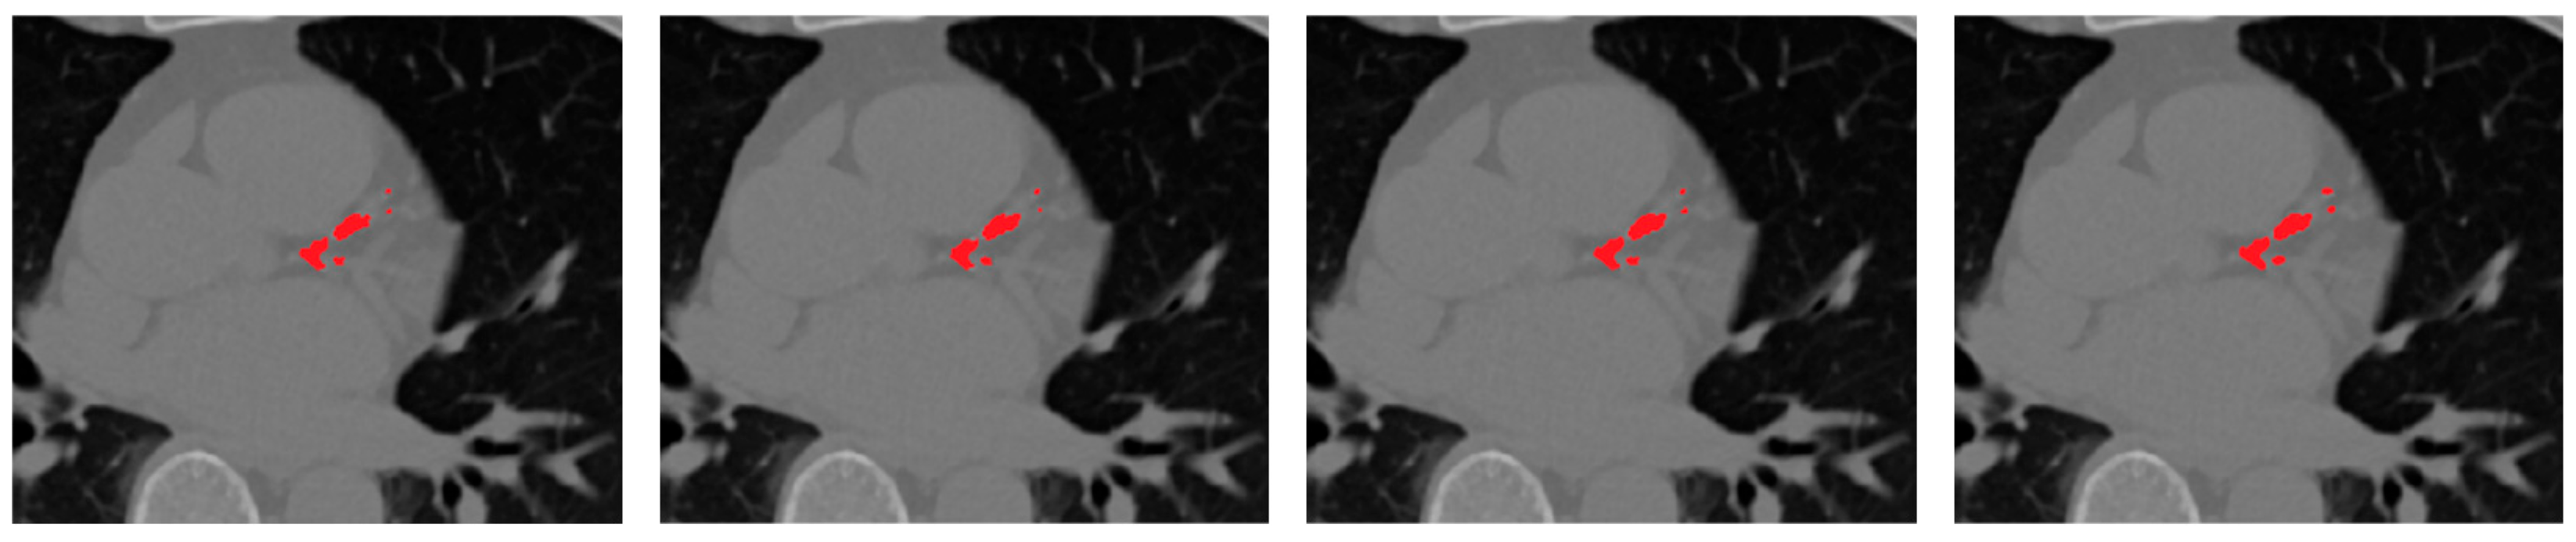

Figure 8 presents qualitative examples illustrating the progressive improvement across different configurations. The final model with vessel priors produces cleaner, vessel-aligned lesion maps and sharper calcification boundaries compared to the baseline and soft-voting ensembles. The addition of selective fusion and vessel priors progressively improves lesion sharpness, vessel conformity, and reduces false positives around extracardiac regions.

Figure 8. Ablation study showing the contribution of each framework component. From left to right: Residual U-Net (baseline), soft-voting ensemble, rank-based selective ensemble, and rank-based ensemble with vessel priors.